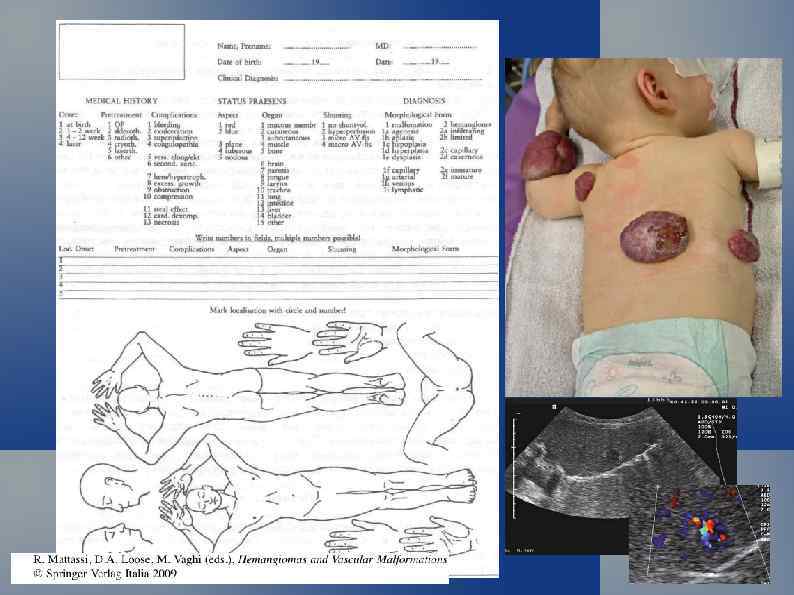

Диссеменированный гемангиоматоз новорожденного